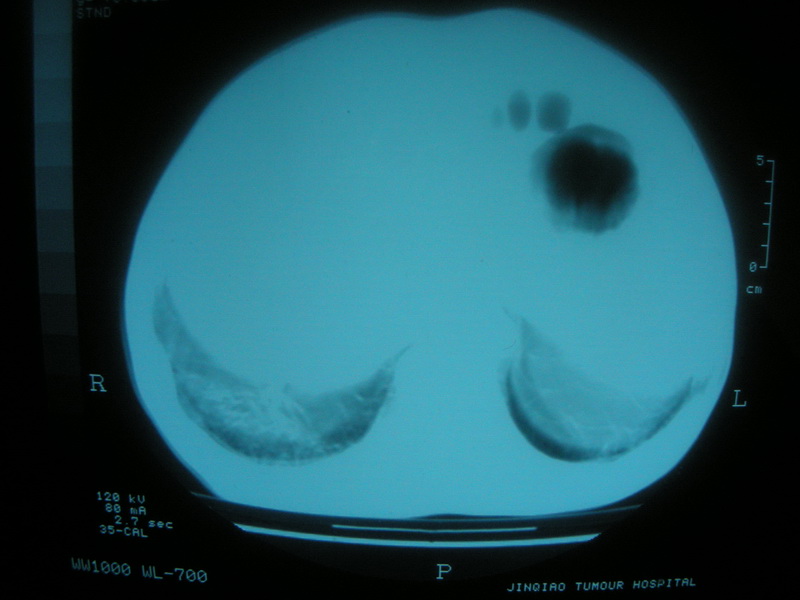

标题: CT11692:男,63岁,糖尿病史15年.抗炎治疗7天,病情 [打印本页]

标题: CT11692:男,63岁,糖尿病史15年.抗炎治疗7天,病情

请老师看看是结核还是炎症?

双肺继发性肺结核伴感染!

双肺继发性肺结核伴支气管播散。